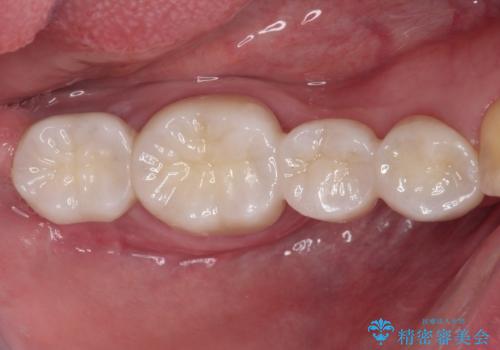

抜歯してからインプラント埋入までには時間がかかるため、その間に下顎左右臼歯の金属のブリッジをオールセラミックへ変えていくこととしました。

目立つ部分の銀歯や気になる変色歯をまとめてきれいに仕上げることができました。